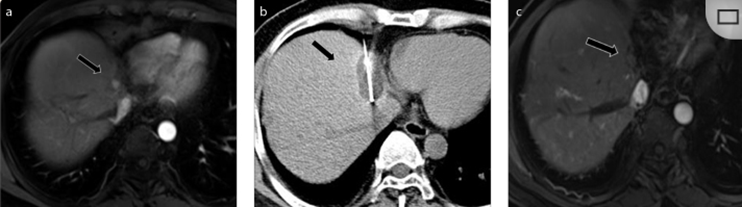

79 歲男性,肝轉(zhuǎn)移(結(jié)直腸癌)腫瘤的完全消融病例

( a ) 軸向 MRI 和 ( b ) 軸向 CT 顯示肝S8段有一個(gè)16mm的病灶,鄰近肝緣。( c )冷凍消融期間CT顯示放置了2個(gè)冷凍探針,低密度冰球包圍病灶。(d)術(shù)后1個(gè)月隨訪 CT顯示冰球?qū)?yīng)的壞死區(qū)域,未見復(fù)發(fā)。(e)術(shù)后6個(gè)月的CT,壞死區(qū)域縮小,未見復(fù)發(fā)。(f)與基線影像(g)相比,12個(gè)月后的FDG-PET/CT顯示未見FDG攝取。

62歲女性,肝轉(zhuǎn)移(卵巢癌)腫瘤的完全消融病例(a)軸向CT顯示病變位置毗鄰心臟和上腔靜脈(黑色箭頭)。(b)術(shù)中軸向CT掃描:使用三個(gè)冷凍探針。1個(gè)月后的軸向(e)和冠狀位(f)增強(qiáng)CT掃描顯示低密度區(qū)域,由于肉芽組織反應(yīng)引起的邊緣增強(qiáng)。